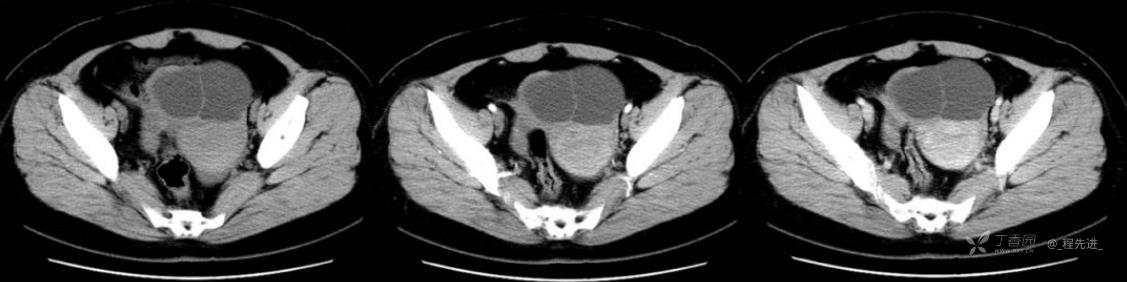

1月特别精彩病例|中老年女性,盆腔包块近半年持续增大【病理已公布】

患者年龄:53岁

简要病史:4年前体检时发现盆腔包块及子宫肌瘤,近半年复查盆腔彩超发现包块持续增大,近1年月经欠规律,伴腰、腹胀。

体格检查:宫颈举痛(+),子宫增大,质地中等,活动可,无压痛;右下腹轻压痛,无反跳痛,左侧附件区未扪及明显包块,无压痛。

阴式彩超:子宫约65*58*44mm大小,子宫肌层可见多个低回声块影,较大的为35*27mm(位于子宫前壁下段偏右侧壁),边界清,内回声欠均匀,后方回声衰减。考虑子宫多发肌瘤。子宫后壁可见一混合回声包块,大小约31*20mm,边界不清,内呈强弱回声,分布不均,考虑子宫腺肌瘤,其他疾患待删。子宫内膜厚6mm,宫颈可见多个囊性暗区,边界清,内透声好,后壁效应增强,较大的为15*11mm。子宫前方偏左侧可探及一大小89*75mm囊性肿块,边界清,壁薄光滑,内透声好,可见分隔光带